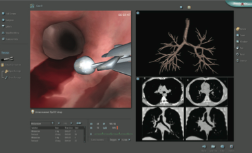

ESSENTIAL EBUS MODULE :

The Essential EBUS module incorporates designated tasks, clinical cases and educational materials.

The tasks are aimed at learning and practicing ultrasound image interpretation, relevant structures and LN stations identification (according to the IASLC 2009 map) and correct workflow of EBUS-TBNA performance.

The clinical cases featuring a comprehensive patient environment, offering the choice of general anaesthetized patient. Diverse virtual patients, each featuring his CT scan, calls for user to take clinical decisions and perform EBUS-TBNA for various lymph node stations.

This module features both curved linear and radial endobronchial ultrasound.